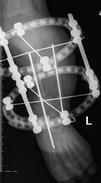

儿童陈旧性孟氏骨折

术后1个月肘关节侧位片

儿童陈旧性孟氏骨折,术前桡骨小头陈旧性脱位,经截骨矫形治疗后1个月,桡骨小头已复位,患儿肘关节屈伸功能(1-2图),前臂旋转功能(3-4图)正常